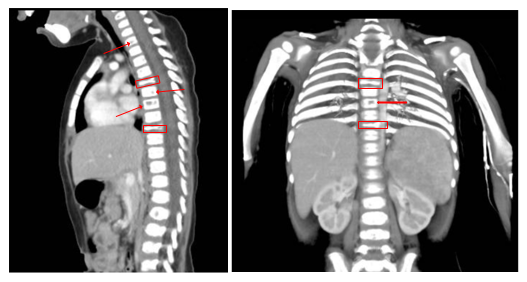

A subsequent CT scan of the brain, complete abdomen, and thorax showed soft tissue lesions that were homogeneous, well defined, and exhibited mild enhancement with contrast, eroding and altering the morphology of the skull cortex without infiltrating the brain parenchyma (Figure 2A & 2B). Additionally, multiple lytic lesions were identified in the sphenoid bone and vertebral bodies of C2, C3, and C5 vertebrae. Thoracic CT revealed lytic lesions in the vertebral bodies of T1, T3, T4, T6, and T7, along with pathological fractures of T5 and T9 (Figure 3A & 3B). Given the extensive bone involvement, the possibility of aggressive systemic disease was considered, including LCH, neuroblastoma, and metastatic rhabdoid tumors. Definitive histopathological examination of the previously biopsied tissue, complemented by immunohistochemistry, confirmed the diagnosis of Langerhans cell histiocytosis (LCH). Immunohistochemical staining was positive for S-100, CD68, PD-L1, and CD1a, which further confirmed the diagnosis. Due to the patient developing bilateral ear discharge, a mastoid CT scan was performed. The scan showed a loss of normal mastoid morphology with bony erosion caused by homogeneous soft tissue lesions bilaterally (right mastoid: 2.9 x 1.8 cm, left mastoid: 3.4 x 2.3 cm) (Figure 4A & 4B). These findings are consistent with the systemic spread of LCH, which affects the temporal bones.

Figure 3A&3B Thoracic CT of the patient revealed lytic lesions in the vertebral bodies of T1, T3, T4, T6, and T7, along with pathological fractures of T5 and T9.